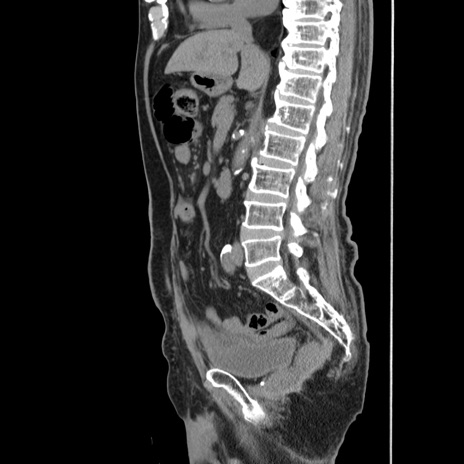

症例24(矢状断像)

【症例】80歳代男性

【主訴】左側腹部痛、嘔吐

【現病歴】本日早朝より左腹部に痛みあり。昼頃嘔吐認めたため、救急要請。

【既往歴】直腸癌(Mile手術)、胆摘

【身体所見】意識清明、BT 35.9℃、BP 221/93mmHg、SpO2 97%(RA) 、腹部:左ストーマ周囲に限局性の腹部膨隆あり。 膨隆部自発痛・圧痛あり・軟。

【データ】WBC 7700、CRP 0.09